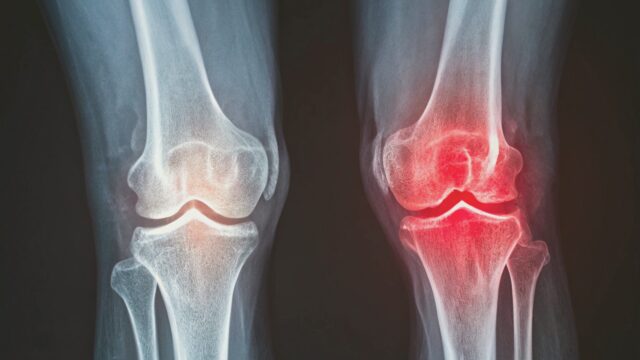

変形性膝関節症は、中高年に多く見られる膝関節の疾患で、日本では約2500万人が罹患していると推定される「運動器の国民病」とも言える深刻な問題です。この疾患は、膝関節の軟骨がすり減ることで炎症が起こり、痛みや機能障害を引き起こします。

体重をかける際に膝にかかる負荷に対して、関節軟骨や半月板に変性や摩耗が年齢とともに生じてきます。膝関節の軟骨がすり減ることで、クッションとしての機能が低下し、骨同士が直接こすれ合うようになります。

MRI研究により、早期段階で骨棘(こつきょく)と呼ばれる小さな突起が半月板を引っ張り、損傷を引き起こすことが分かってきました。

関節のすり減りが繰りかえされると、軟骨の削りかすの様な破片が関節内に散らばります。この小さな破片が関節包にとりこまれることによって、この異物を排除するための炎症反応が生じます。

軟骨の消失に伴い、骨の形状が変化し、骨棘が形成されます。